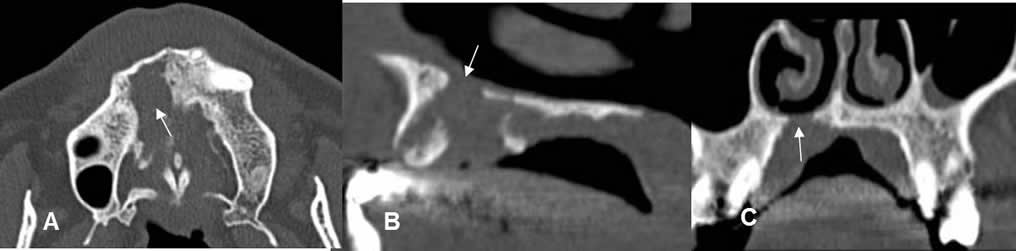

Fig 70. Tumor.

A: TAC axial, B: TAC reconstrucción sagital y C TAC reconstrucción coronal. Lesión lítica que erosiona el paladar duro, por tumor escamocelular.